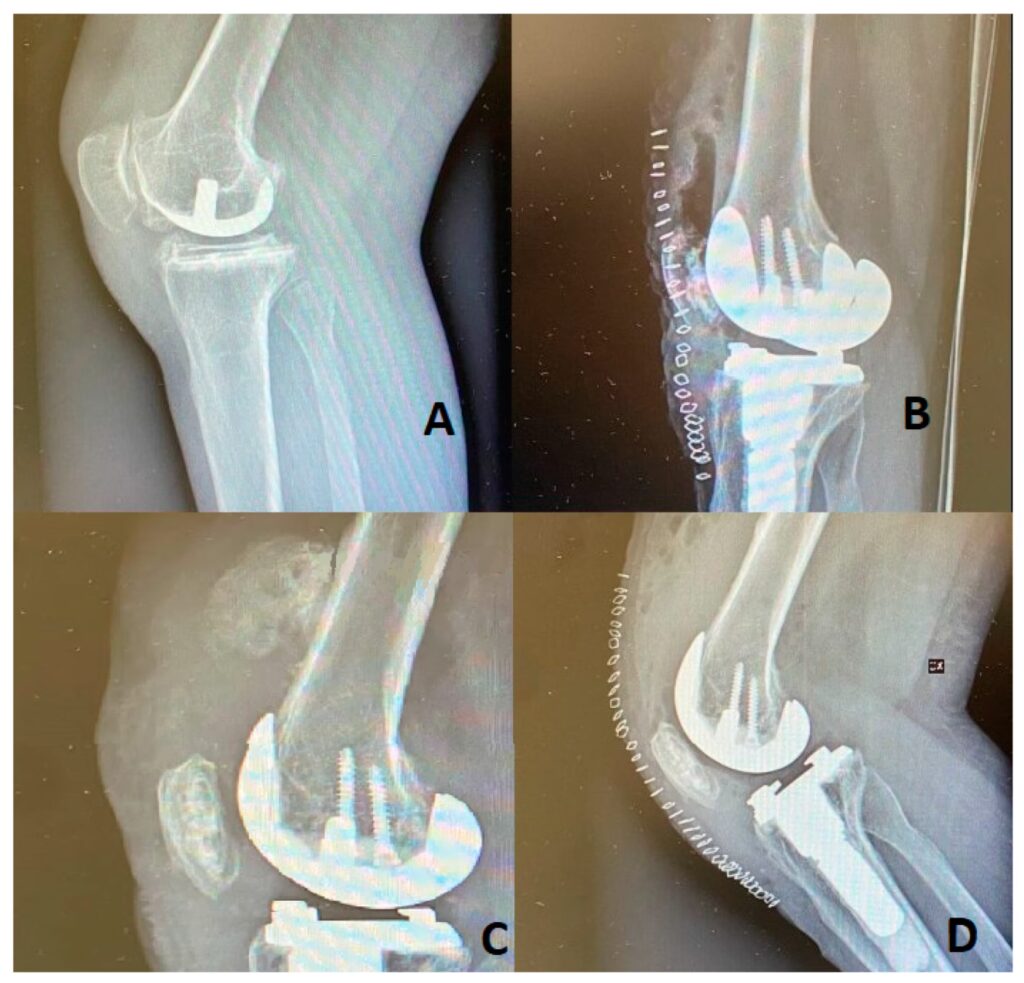

Kirurgisk behandling

Når smerterne er uudholdelige, og andre behandlinger ikke længere virker, kan operation komme på tale. Den mest almindelige operation er en ledudskiftning (alloplastik), hvor det ødelagte led erstattes med et kunstigt led af metal og plastik. Hofte- og knæoperationer er de mest almindelige og har en meget høj succesrate.